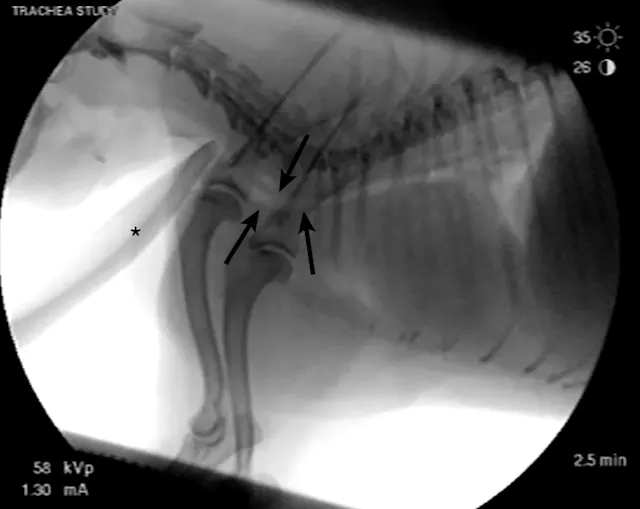

On examination, the dog was panting with expiratory effort and crackles auscultated diffusely. She exhibited an occasional goose-honking cough and retch. Her body temperature was normal. Radiography (Figures 1 and 2), fluoroscopy (Figure 3), and bronchoscopy (Figures 4 and 5) were performed.

Bronchoscopy revealed moderate grade 2 (40%-50%) extra-thoracic airway collapse, with grade 4 (100%) collapse of the intrathoracic airway (most severe at the carina). Marked diffuse purulent discharge was observed throughout the trachea and mainstem bronchi along with grade 3 to 4 (75%-100%) collapse of proximal bronchi (left cranial, right cranial, and right middle), with thickened mucosa and blunted airway divisions throughout. The caudal airways (left and right) were less affected distally.